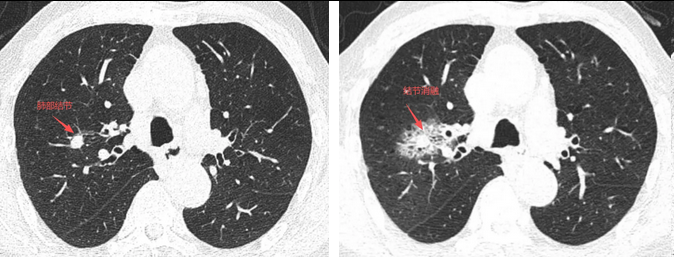

▲患者术前CT(左侧),箭头处为肺结节;术后CT(右侧),结节消融后的改变